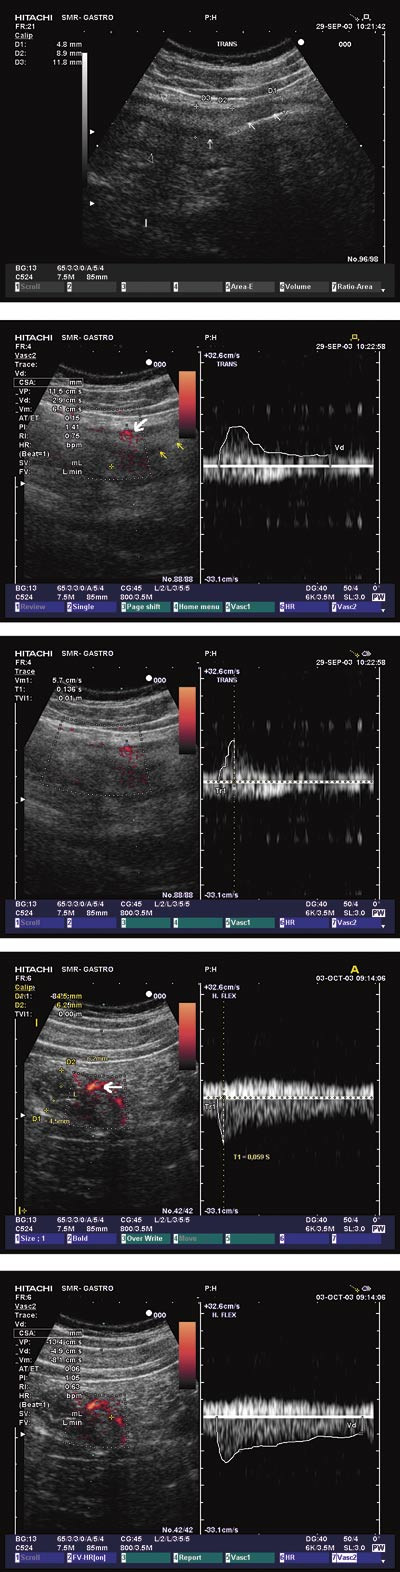

I den affiserte delen av colon viste todimensjonal ultrasonografi transmurale forandringer hos alle pasientene, med opphevet ultrasonografisk lagdeling og redusert eller opphevet peristaltikk samt luft eller væskeansamling proksimalt for det iskemiske området. I akuttfasen var veggtykkelsen 9,0 ± 1,7 mm, ved kontroll 4,2 ± 0,7 mm, p < 0,0005. De sonografiske forandringene viste mer utbredt patologi enn det man kunne påvise ved endoskopi, både i tarmens lengderetning og tverrsnitt.

Power-doppler

Signalene var asymmetrisk lokalisert i tarmveggen. I akuttfasen ble det registrert sterke signaler hos to pasienter, hos de øvrige var det svake signaler (e-fig 2). Ved kontroll var signalene ikke mulig å påvise hos tre pasienter, for øvrig var de uendret.

Resistensindeks

I akuttfasen var resistensindeksen i murale blodkar 0,72 ± 0,08, ved kontroll 0,62 ± 0,09, p = 0,010.

Systolisk akselerasjonstid

I akuttfasen var systolisk akselerasjonstid i tarmen 0,144 ± 0,054 ms, mens den ved kontroll ble målt til 0,070 ± 0,023 ms, p = 0,001. Systolisk akselerasjonstid i mesenterielle kar kunne måles hos ni pasienter, og var 0,070 ± 0,010 ms – nærmest identisk med det som ble funnet i tarmveggen ved kontroll (p = 0,969). Hos to pasienter med høyresidig kolitt ble målingene gjort i a. mesenterica superior, mens resten av målingene ble gjort i a. mesenterica inferior.

I denne studien (fig 3) ble den maksimale veggtykkelsen i tarmen halvert i løpet av få dagers observasjonstid. Systolisk akselerasjonstid i murale kar (som i motsetning til resistensindeks ikke tar hensyn til blodets hastighet i diastolen) ble også halvert i løpet av observasjonstiden, og ble samtidig sammenfallende med tilsvarende målinger i de tilførende mesenterielle karene. Dette parameteret er så vidt vi kjenner til ikke tidligere beskrevet ved akutt iskemisk kolitt, men synes å kunne være et godt supplement til resistensindeks dersom man ønsker å analysere de hemodynamiske forandringene ved denne sykdommen.